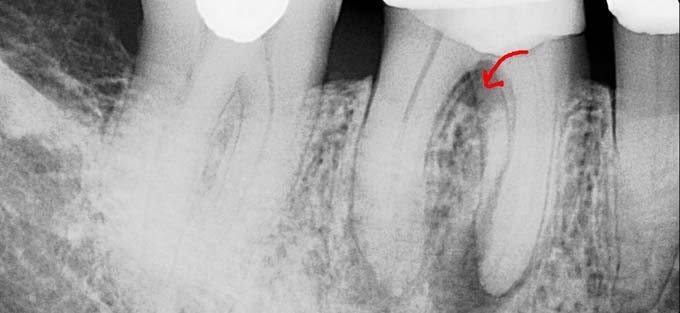

- рентген с применением контрастного вещества;

Рентгеновский снимок с контрастированием выполняется прицельно, в 2D формате. Прицельный рентген отличается от панорамного небольшим объемом изображения — пара соседних единиц рядом с исследуемым. На снимке можно увидеть очаг прикорневого воспаления, а также проанализировать состояние запломбированных каналов.

При перфорации зуба в области видимой части коронки диагностика не представляет затруднений, поскольку дефект заметен даже невооруженным глазом. Если же есть сомнения в наличии осложнения, либо она произошла в области дна зубной полости, то необходимо проведение рентгенологических снимков с контрастированием (например, в качестве контраста может выступать штифт или файл).